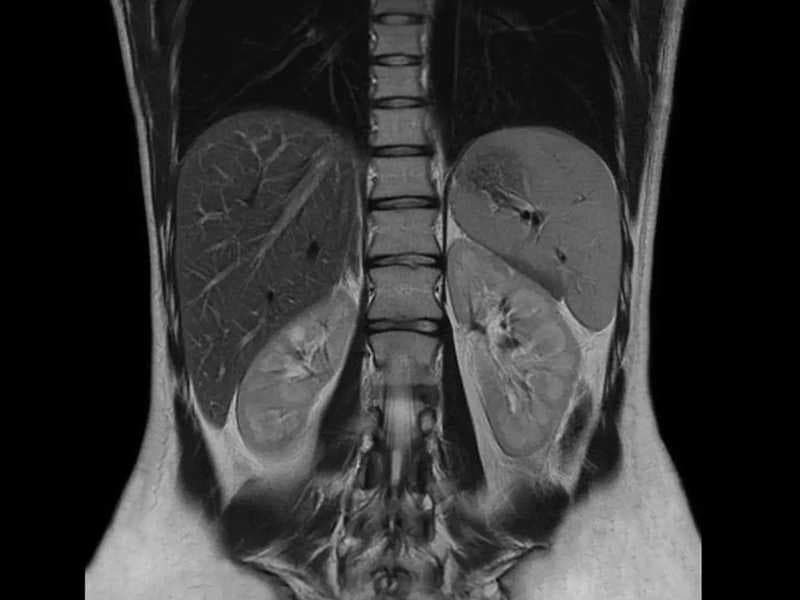

Secure your health with an Upper Abdominal MRI! Experience the difference of early diagnosis with our detailed MRI imaging service accompanied by expert radiologists.

Detailed examination of the liver, pancreas, gallbladder, and kidneys with Upper Abdomen CT Scan. Advanced medical imaging center and radiology services for reliable results.